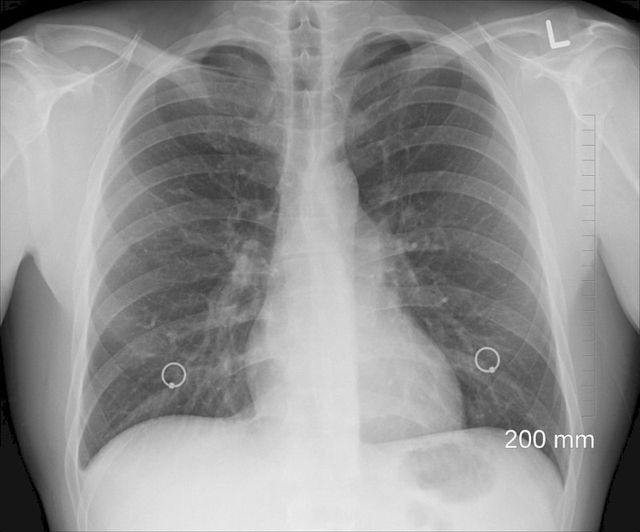

Пострадавший сегодня днем после нападения неизвестных екатеринбургский общественник Алексей Беззуб проходит медобследование. Врачи уже диагностировали у него перелом ребра.

«Нахожусь в больнице. Диагностировали перелом ребра. Сейчас еще к нейрохирургам пойду — надо посмотреть, что с головой. Потом обязательно напишу заявление в полицию — отмораживаться, как и менять свою гражданскую позицию, не собираюсь», - сообщил общественник корреспонденту ЕАН.